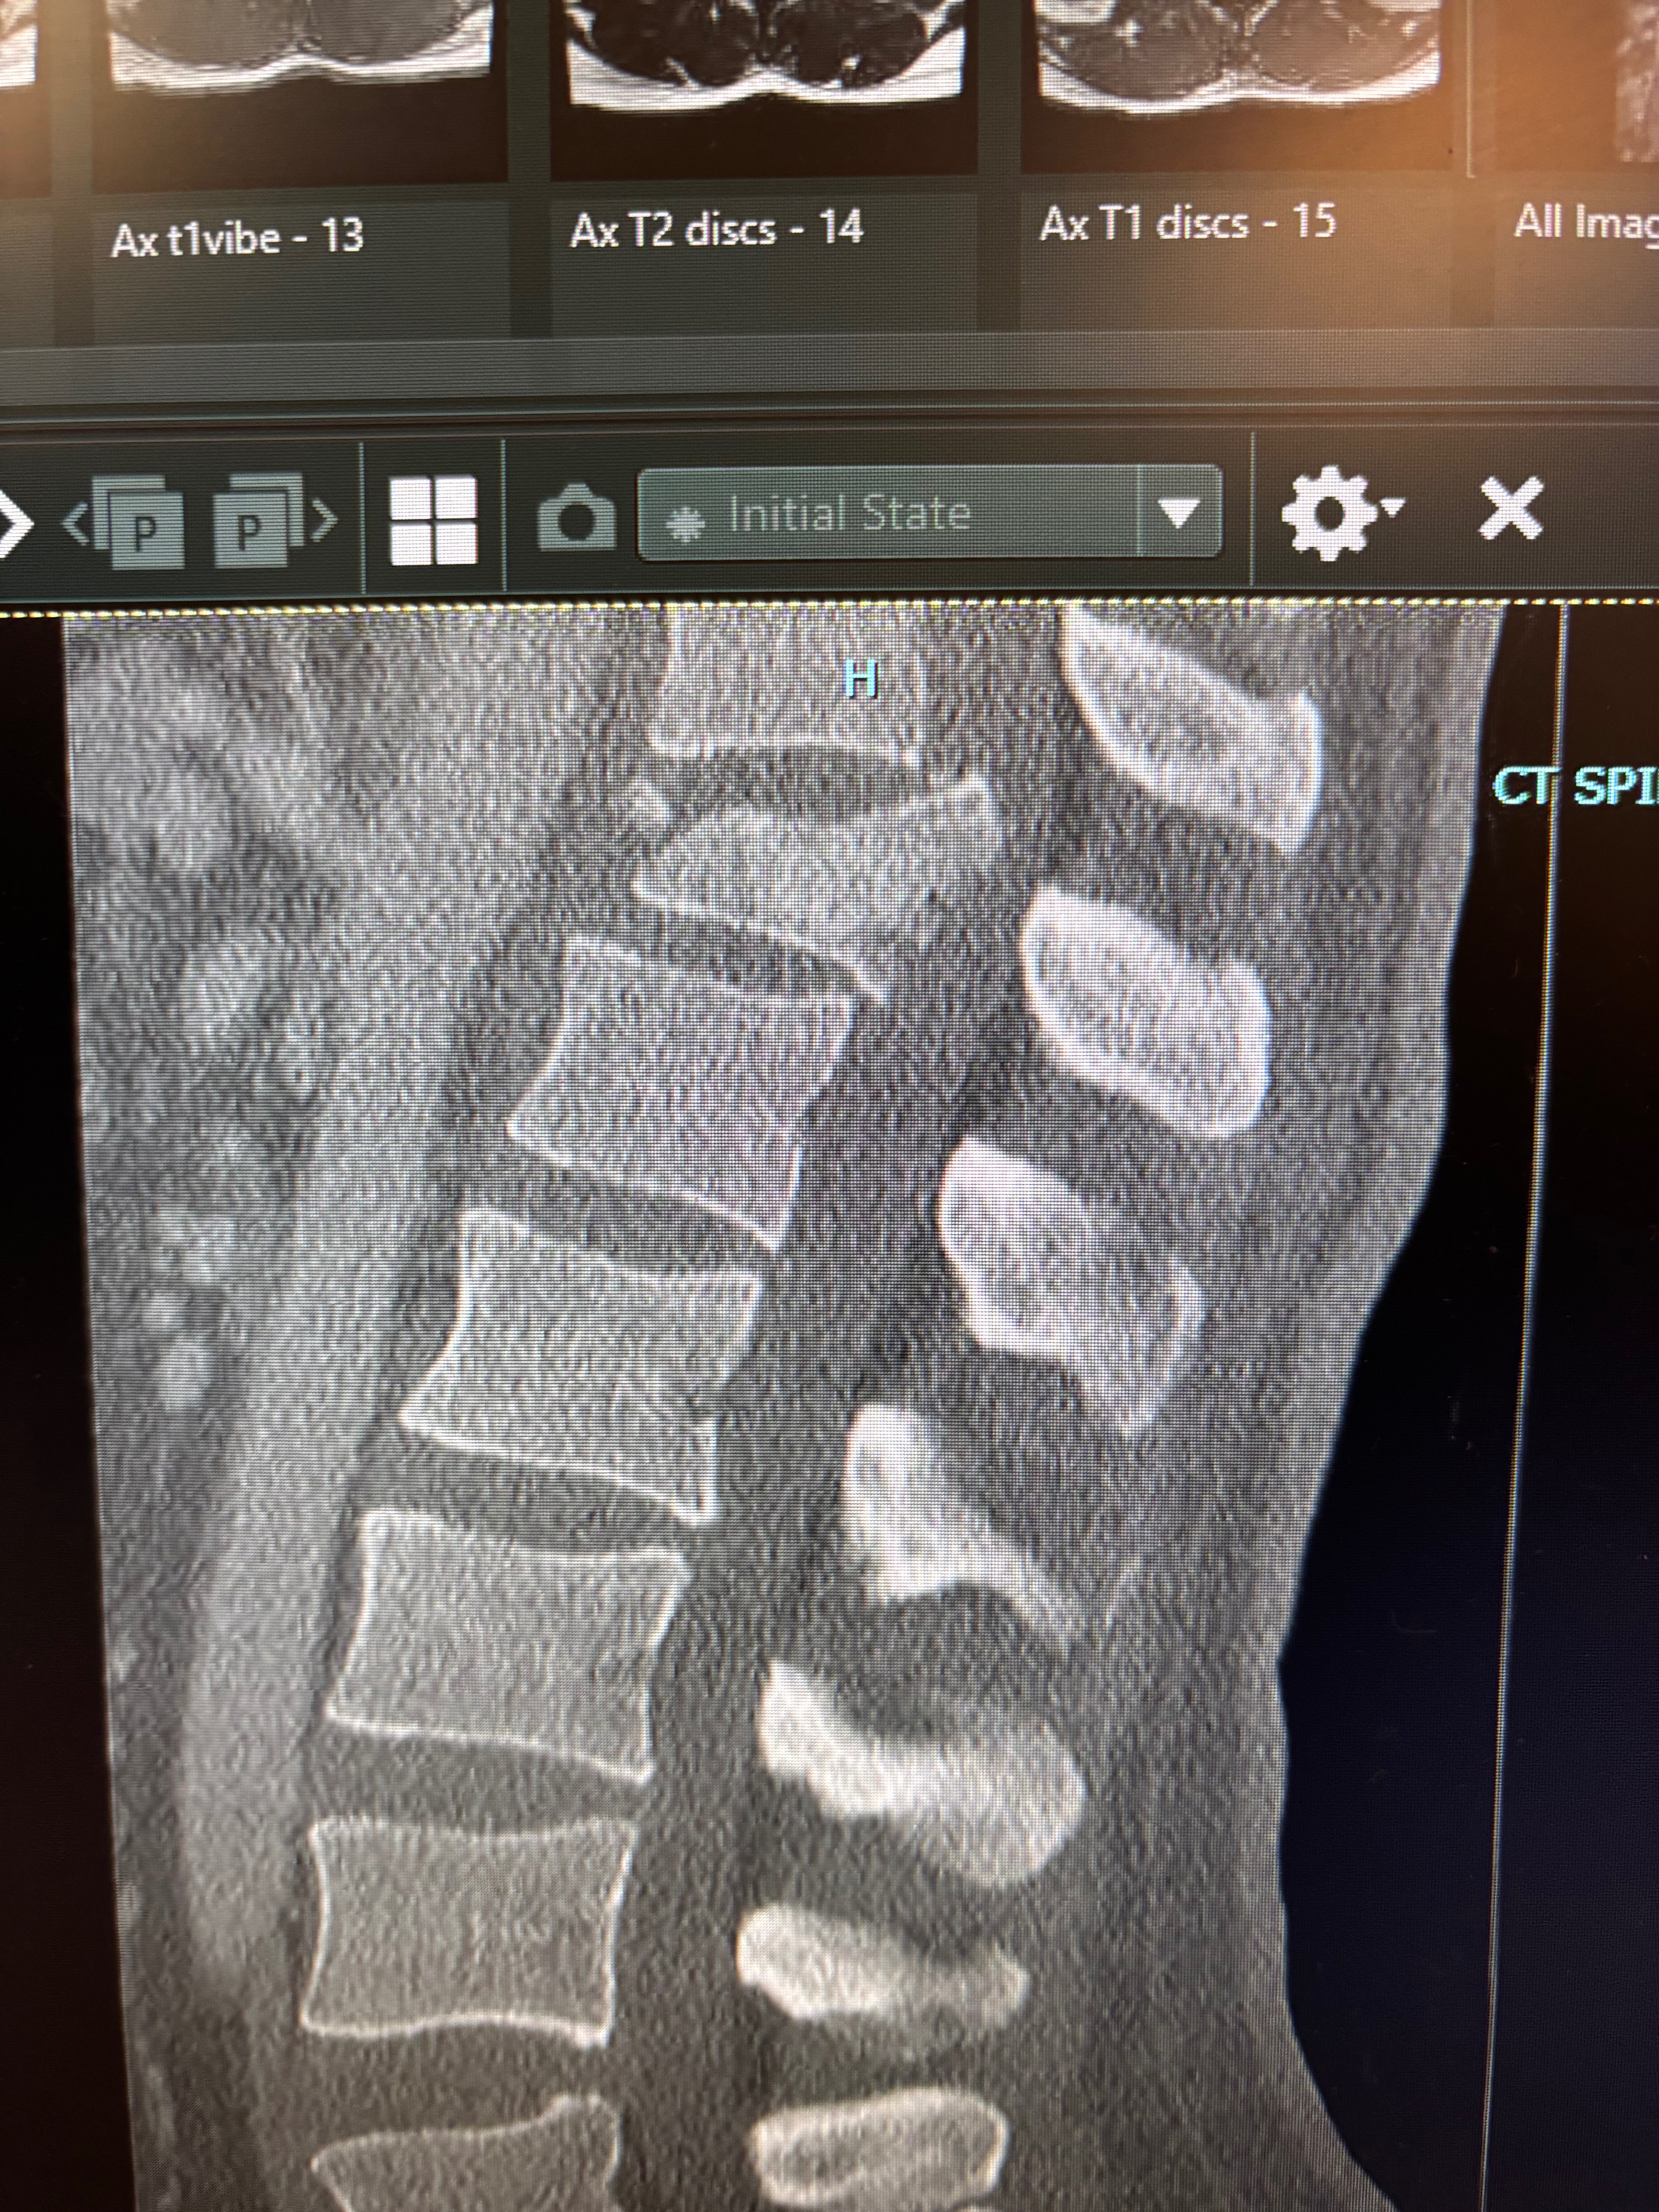

Slavic suffered a burst fracture to his T12 vertebra, with bone fragments pressing on his spinal cord. There’s potential permanent spinal damage, and pinched nerves are also suspected.